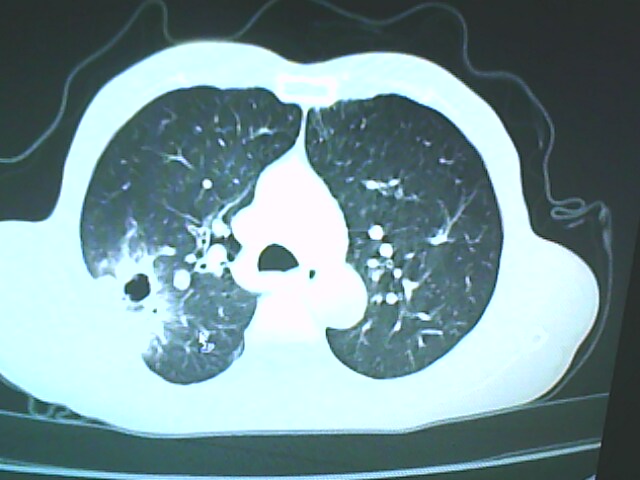

患者,男,66岁,以咳嗽、咳痰伴胸痛来就诊。

胸片提示右上肺占位病变。请各位老师看看ct。

请各位老师看看,考虑:癌性空洞吗?

考虑癌性空洞可能性大,空洞内壁不规则,病灶周围模糊,分叶、有毛刺

空洞内壁不规则,病灶周围模糊,分叶、毛刺呈日光放射状,突然截断,支持考虑癌性空洞

考虑右肺上叶后段周围型肺癌并癌性空洞形成。

考虑癌性空洞可能性大,内壁不规则,洞壁薄厚不均呈结节状突起,边缘模糊,分叶,毛刺

右上肺后段肺癌:

典型癌性空洞(偏心性,壁厚薄不均,内壁不光整),周围毛刺较僵硬,且有刺突征和血管聚集征